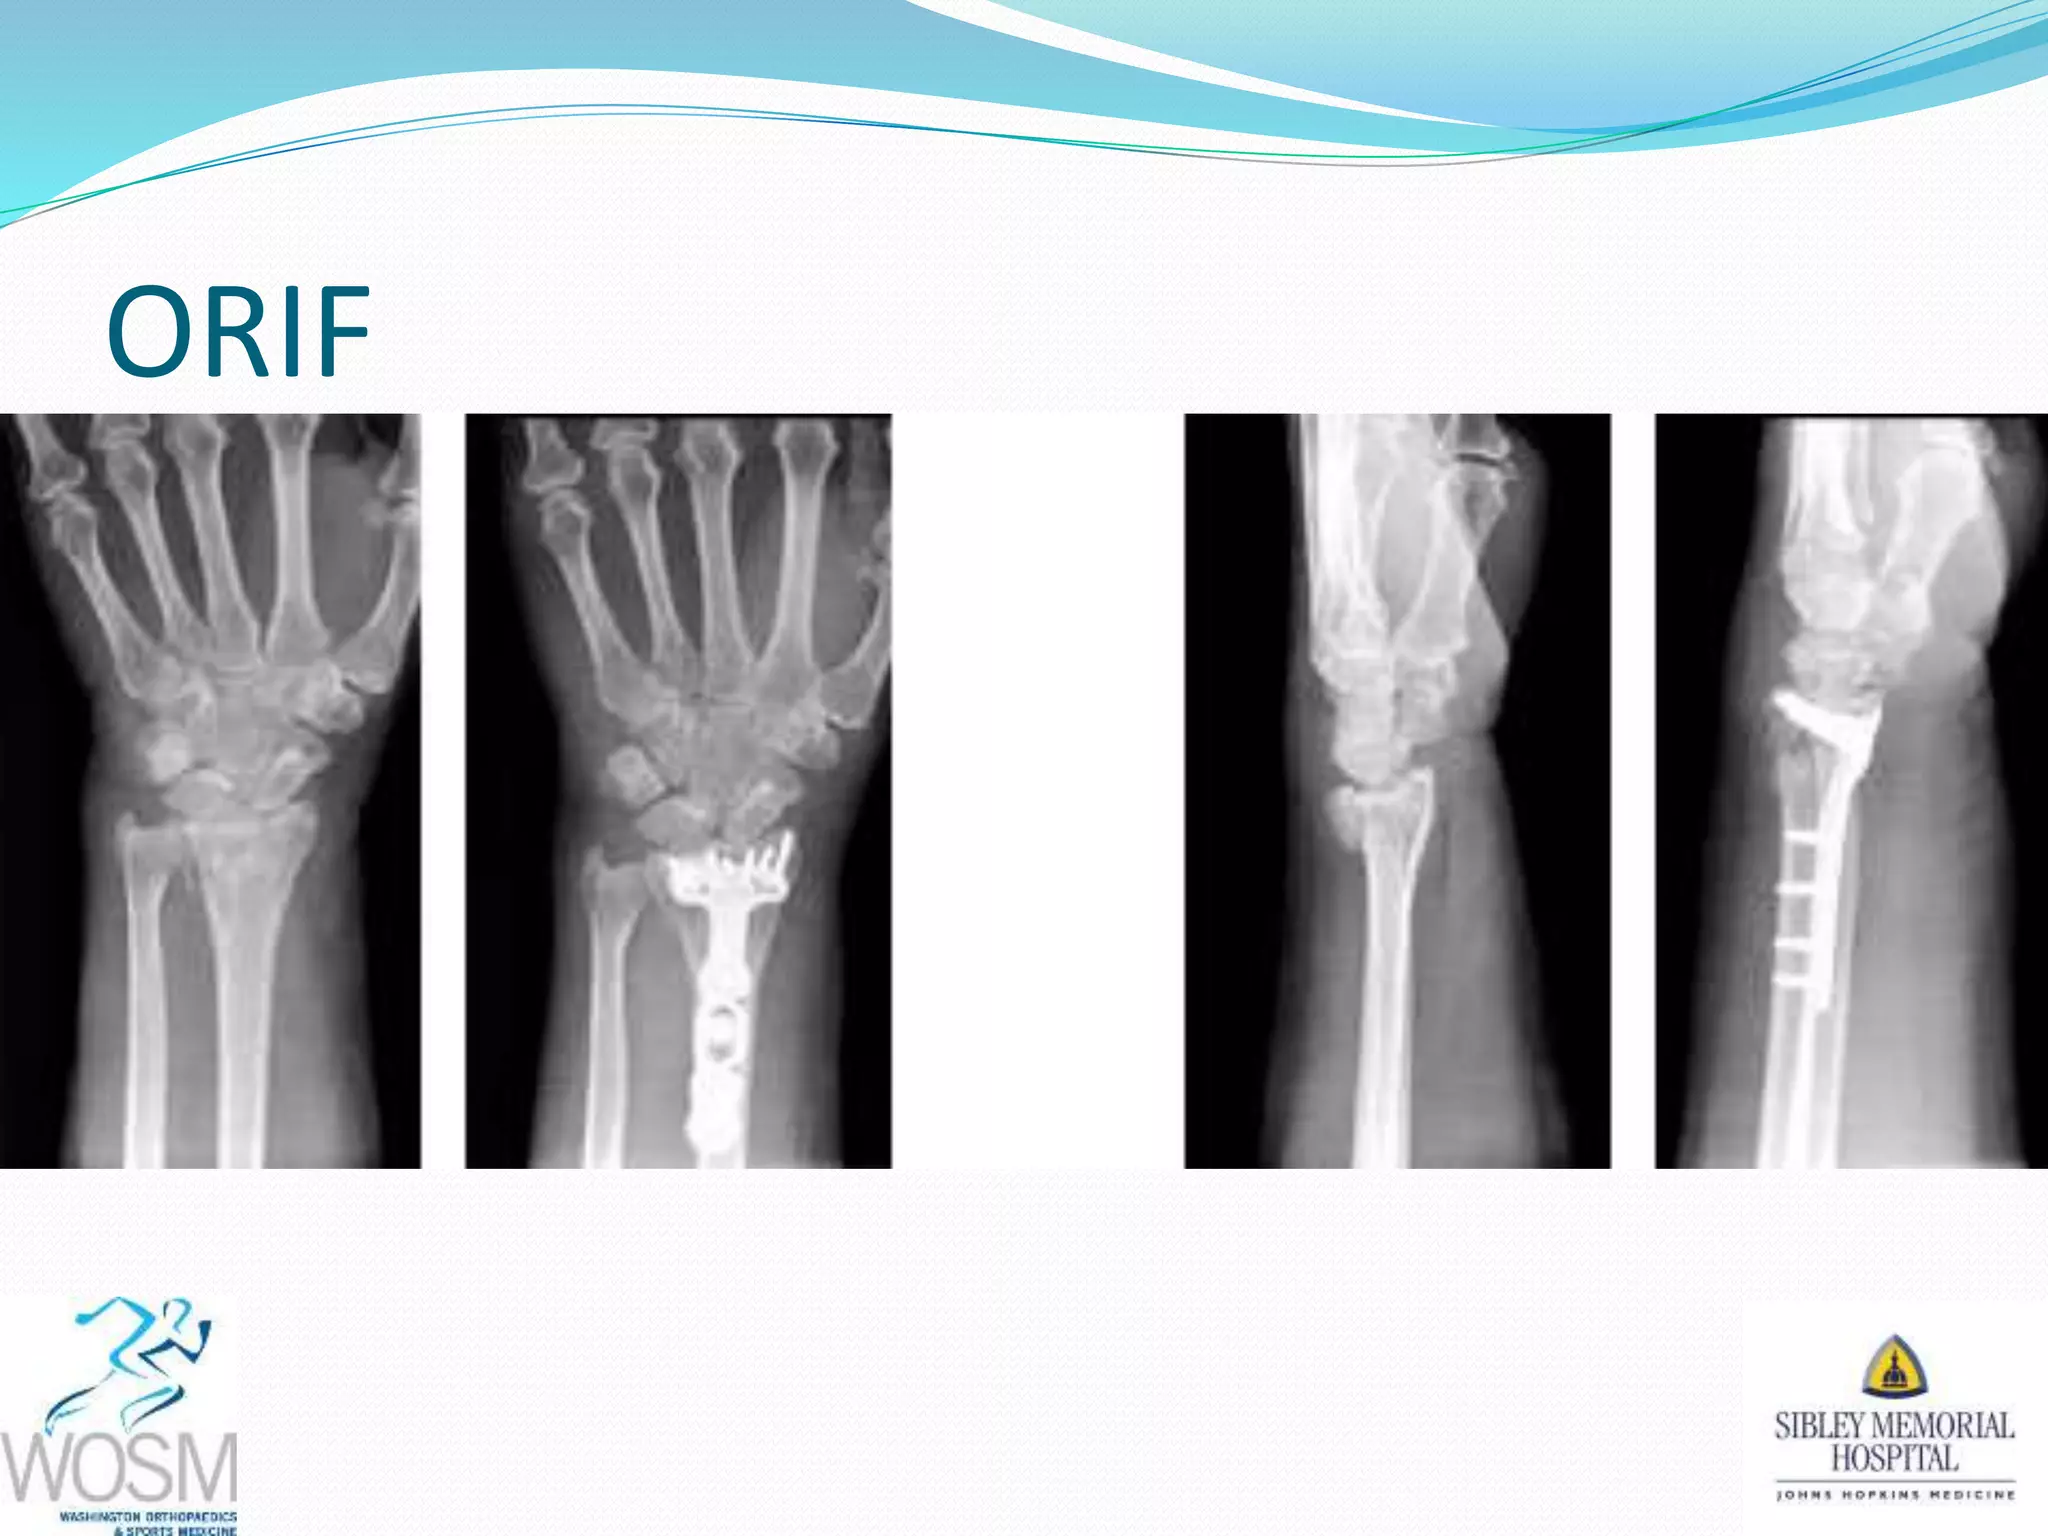

This document discusses wrist fractures, including who is most at risk, common causes, signs and symptoms, treatment options, and prevention. The elderly and those with osteoporosis are most prone to wrist fractures due to falls. Treatment may involve splinting, casting, closed reduction, or surgery depending on the fracture. Maintaining bone health through medication, vitamins, exercise, and diet can help prevent wrist fractures.